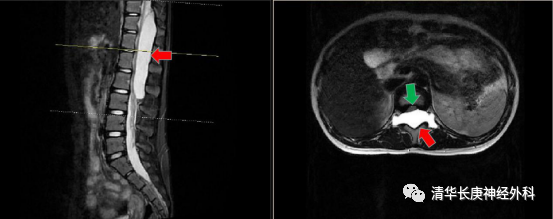

术前磁共振示巨大椎管内囊肿(红色箭头),受压的脊髓(绿色箭头)